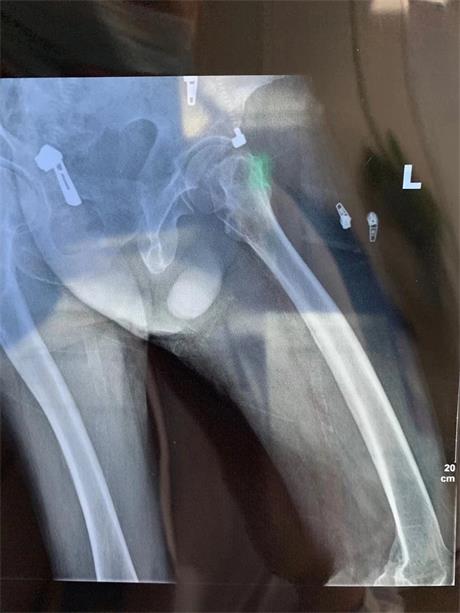

李爷爷家住东莞长安镇,有脑梗病史的他曾多次来乌沙医院内科住院治 疗,蕞近一次发作是在2017年。去年12月9日,李爷爷走路时不慎摔倒,当时感觉左髋部疼痛。伤后7小时,患者症状加剧、站立困难,出现左下肢活动障碍,家属赶紧将老人送来他们蕞信任的乌沙医院。接诊医生详细查体并询问病史,CT检查提示左枕顶叶脑软 化灶、出现脑萎缩,DR检查提示左侧股骨颈骨折,当天收入外二科(骨科)住院治 疗。

患者影像学检查资料